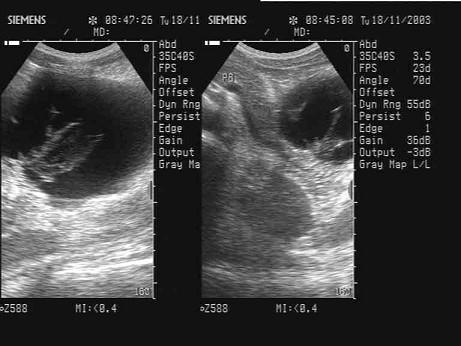

问题 患者,女,42岁。3周前患急性胰腺炎,并给予治疗,现超声复查胰腺如图,诊断为?(?)

选项 A.急性胰腺炎 B.胰腺真性囊肿 C.胰腺假性囊肿 D.后腹膜肿瘤 E.胰腺囊腺癌

答案 C